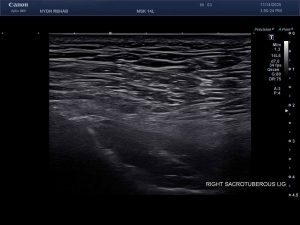

Ultrasound Images of SIJ Ligaments

• Sacrotuberous ligament thickening and enthesopathy